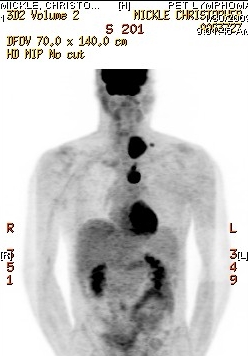

PET scan 0/30/09 Mon 2/9/2009 - Here is an image from Chris' latest PET scan. The dark sections on either side in the mid-abdomen are his kidneys which are fine. Note the large tumor on the left side of his neck. This is the one that is giving him such a hard time. The area below his diaphragm that was targeted with radiation already seems to be clear as does the spot on his lung.